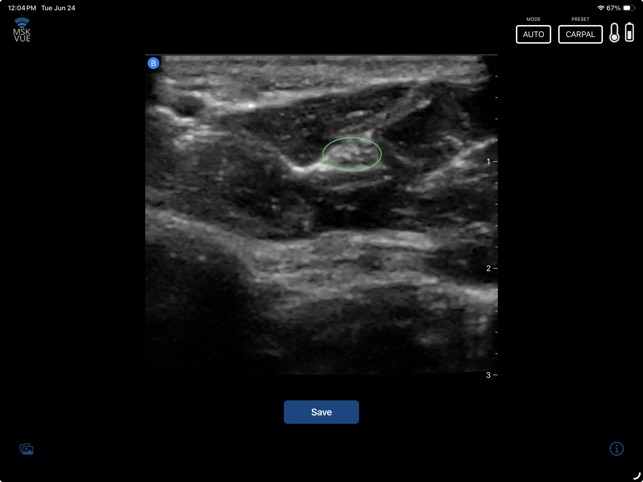

MSK VUE is a specialized training application for musculoskeletal ultrasound. The system utilizes an artificial intelligence component to support the identification of key peripheral anatomical structures within an interactive, simulated ultrasound imaging environment. The interface is designed to present visualizations of nerves, tendons, and bones, allowing users to engage with the simulated data. This application's core mechanism focuses on presenting specific anatomical targets and facilitating their recognition through its AI-driven framework, providing a platform for practice in a non-clinical context.

This application is designed for clinicians seeking to develop proficiency in musculoskeletal ultrasound. It functions as a supplementary educational tool for practicing the identification of peripheral anatomical structures within a simulated environment. This app is intended for educational purposes and does not replace professional medical advice, diagnosis, or treatment; the provided description explicitly prohibits its use in any clinical setting or for any clinical purposes.